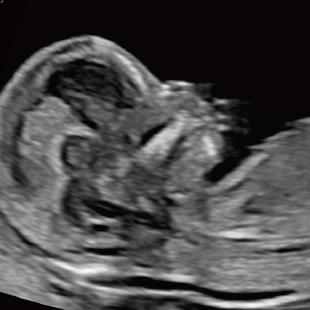

Voluson Expert 22®(GEHealthcare)という産婦人科領域におけるハイエンド超音波診断装置を使用しています。 従来機種と比べ、より高精細な画像描出性能と高度な解析機能を備えており、 胎児の発育や形態をより詳細に観察することが可能です。